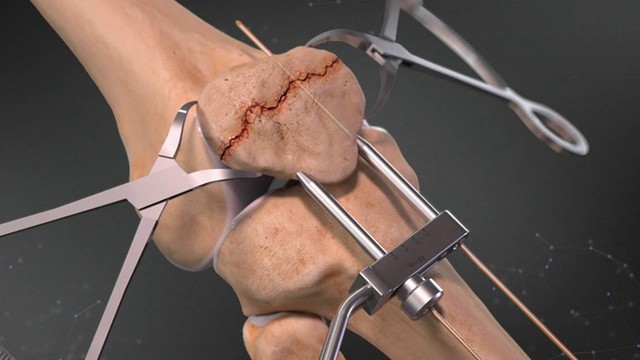

Nguyên nhân, kỹ thuật chẩn đoán gãy xương bánh chè. Giải đáp: Gãy xương bánh chè có phải mổ không.

Gãy xương bánh chè thường gặp khi bệnh nhân ngã và khuỵu đầu gối xuống đất. Chấn thương này chiếm 2 - 4 % tổng số ca gãy xương. Vậy gãy xương bánh chè được định nghĩa như thế nào và làm sao để điều trị chấn thương này hiệu quả? Hãy đọc bài viết dưới đây của nhà thuốc Long Châu để tìm được câu trả lời nhé.